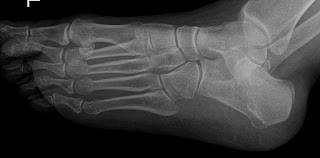

En la radiografía se pueden observar si se observa con detalle una fracturas de los cuellos de los metatarsianos 2º a 4º, un poco más desplazado el del 2º, pero con una alineación aceptable. la paciente fué inmovilizada con una férula posterior y así acudió a nuestra consulta. Cuando vi el caso me pregunté, si cuando se realiza una osteotomia tipo weil percutánea el efecto logradoes similar al que se ha producido de una manera espontánea en este caso, y se puede inmovilizar con un vendaje corrector y le permitimos que ande para colocar las cabezas metarsianas en su sitio, ¿porqué no lo podiamos hacer en esta caso?, de hebho la mujer dice que tenía metatarsalgia antes del golpe, por lo que haciendo un chiste podriamos decir que se ha operado ella sola y sin anestesia.